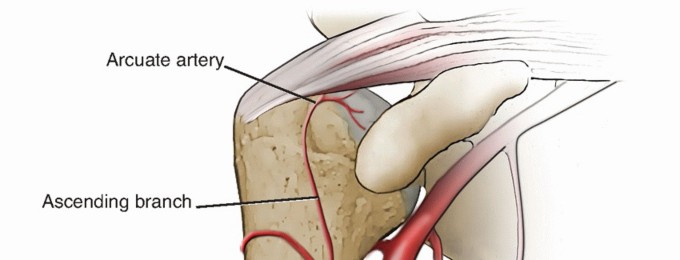

DEFINITION Fractures involving the proximal region of the humerus that provide the supporting framework for t…